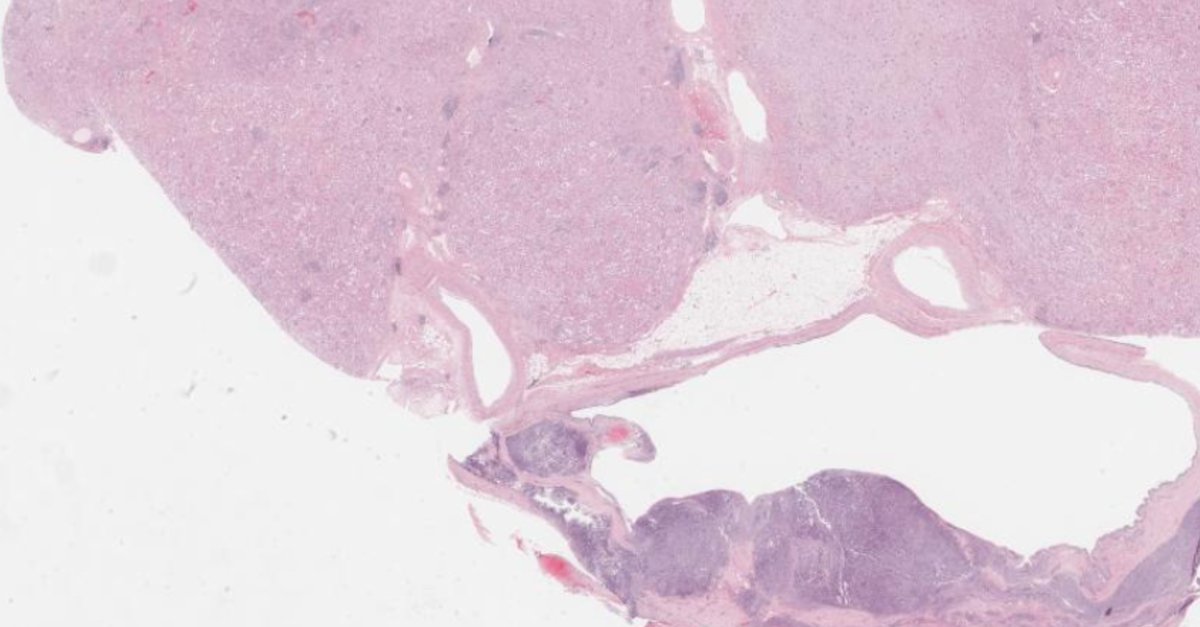

This month’s case challenges your diagnostic eye: a 1 cm well-circumscribed cortical lesion, no necrosis or vascular invasion, and a partial nephrectomy performed. Explore the histology and test your interpretation with this case by Haiyan Qiu, MD: https://t.co/kYa08bpusT